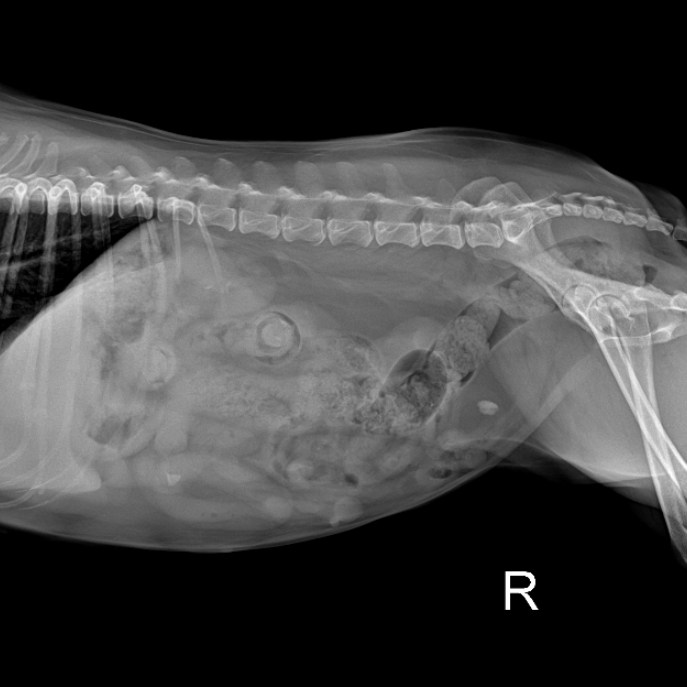

本案例是四月初來本院就診的雪納瑞,經朋友介紹至本院由陳博駿院長做健康檢查,原本以為只是年紀大了活力下降,結果意外檢查出脾臟發現有2.3*2.7公分的腫瘤,主人也很信任,馬上安排手術時間。

所幸手術進行非常順利,切除的脾臟腫瘤與超音波檢查時的大小一致(幸好有做健康檢查),手術後也一併針對牙周病進行洗牙及治療,恢復期間使用高壓氧治療,恢復非常迅速,可看到寵物在高壓氧治療中的笑容

腫瘤切片的結果是惡性的血管肉瘤(Hemangiosarcoma),是脾臟最常出現的惡性腫瘤

,幸好及早發現並切除,主人已做了最好的決定,後續治療的問題就交給萌寵煩惱吧![]()